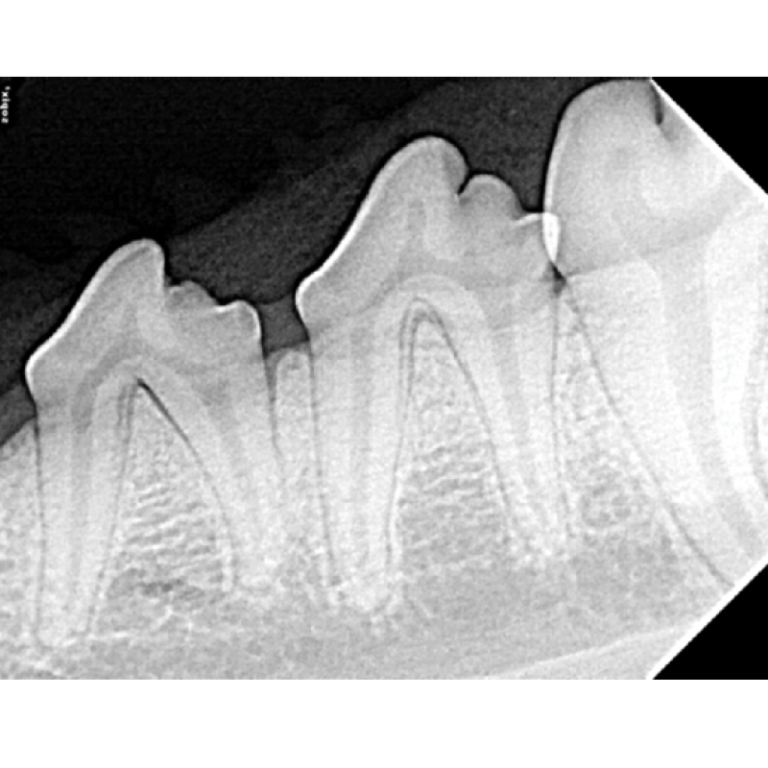

Dental XRay Positioning Guide Feline Mandibular Molars and Premolars D.A.V.I.D. XRAY Dental X Ray Positioning Slideshare there are several types of dental radiography procedures, including intraoral radiographs like bitewings and. *think of dental radiographs as a “shadow” of the root of the tooth* *you. ideal positioning requirements • the film packet should be positioned with its long axis vertically for incisors and. Aim at the area between finger and thumb. The patient's midsagittal plane. Dental X Ray Positioning Slideshare.